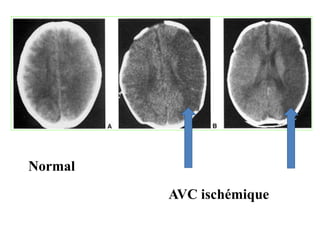

TDM :

– J1 : Examen TDM normal /début d’évolution

– J2 à j8 : aspect le plus typique

– Effacement des sillons corticaux à un stade précoce

• Zone hypo dense ,mal limitée , grossièrement triangulaire

à base externe avec effet de masse

Normal

AVC ischémique

LES ACCIDENTS VASCULAIRESCEREBRAUX : AVC • AVC ISCHEMIQUE: RAMOLLISSEMENT: – C’est une urgence diagnostique et thérapeutique – Le traitement spécifique est la thrombolyse intraveineuse ou la thrombectomie (- de 4h) – Zone d’infarctus ou de ramolissement systématisée dans le territoire de l’artère occluse TDM : – J1 : Examen TDM normal /début d’évolution – J2 à j8 : aspect le plus typique – Effacement des sillons corticaux à un stade précoce • Zone hypo dense ,mal limitée , grossièrement triangulaire à base externe avec effet de masse

• 45.

– j8 àj15 : 2ème semaine : l’hypodensité devient plus homogène et de contours plus nets Au delà de la 2ème semaine : • régression progressive de l’hypodensité • Parfois, persistance de séquelles = atrophie ou cavité porencéphalique • IRM++++ : plus sensible et plus précoce que la TDM • Détecte des infarctus de petite taille • Donne l ’étendue et la gravité de l’infarctus dés les premières heures (Séquence de DIFFUSION+++++) • SEQUENCES: • T1/ T2/ T2 FLAIR/ T2*/séquences morphologiques • Diffusion avec cartographie ADC+++(séquence fonctionnelle)

Hyposignal T1 HypersignalT2 et FLAIR • Diffusion : Hypersignal diffusion (restriction de la diffusion) Oedème cytotoxique++++  ADC Bas • T2 FLAIR:(fluid attenuated inversion recovery) == AVC constitué en hyper signal franc(œdème) • Angio-MR: du polygone de Willis : pour visualiser les artères occluses en hyposignal ( artères circulantes normales apparaissent en hyper signal )